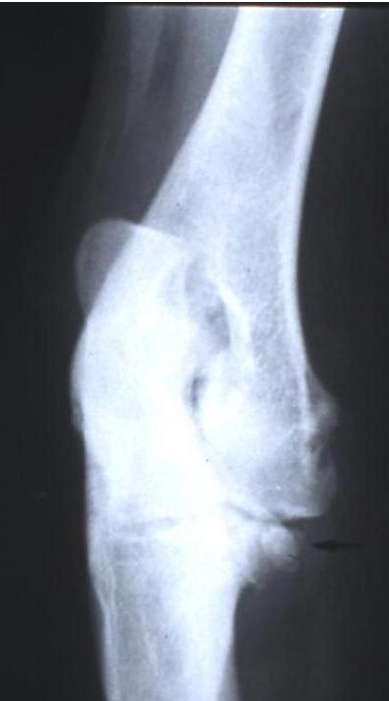

Fractura por localización que ocurre principalmente en animales adultos y afecta las terminaciones distales del húmero, fémur, o tibia proximal